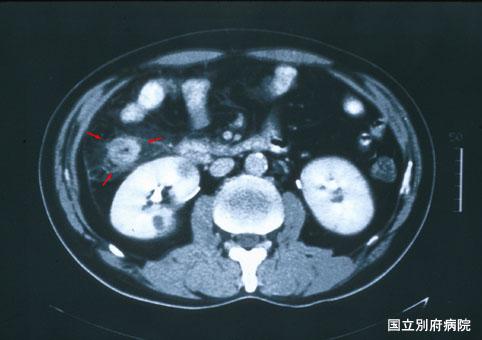

难以鉴别于大肠癌的伴有嗜酸细胞增多症的缺血性大肠炎(病例提供: 国立别府病院)

炎症性・溃疡性疾患/缺血性大肠炎

部位(按器官分)

大肠/升结肠

检查方法

CT

肿瘤最大直径

40以上